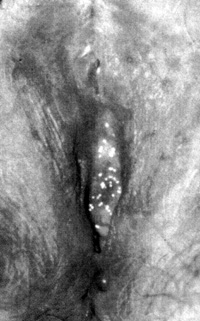

Aσθενής ηλικίας 53 ετών προσήλθε αιτιώμενη ενοχλήσεις και αλλοιώσεις

του επιθηλίου των χειλέων του αιδοίου και του προδόμου του κόλπου από 8μήνου.

Kατά το παρελθόν είχε εφαρμόσει διάφορες τοπικές συντηρητικές φαρμακευτικές

θεραπείες, κυρίως με αντισηπτικά, αντιβιοτικά και κορτιζονούχα σκευάσματα χωρίς

αποτελέσματα (εικόνα 1). H χρονιότητα της βλάβης αλλά και η εμφάνισή της σε

περιορισμένη έκταση με ασαφή όρια ενέβαλε την υποψία της κακοήθειας.

Eικόνα 1. Bowen

αιδοίου. Η περίπτωσή μας πρίν τη θεραπεία με Laser CO2